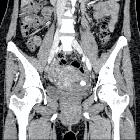

Radiographic features